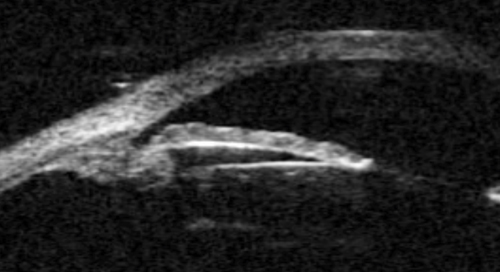

A large or anteriorly subluxated lens, especially in a small eye, may result in phacomorphic angle closure. The lens pushes the iris forward resulting in angle closure and obstruction of the trabecular meshwork. (Figure 3). Lens swelling may result from an intumescent cataract, traumatic injury or simply an age related thickening of the lens in small eyes. In such cases, cataract surgery is usually required. UBM may be used to visualise the lens size and position and to evaluate the iris configuration (Figure 3b).

Figure 3a: Phacomorphic glaucoma. Axial image of anterior segment.

This shows that the anterior chamber is shallow and the iris has a markedly elevated lens vault

caused by a thickened and anteriorly positioned lens. The iris has significant irido lenticular contact.

Figure 3b: Phacomorphic glaucoma. Lenticular profile where the iris follows the shape of the anterior surface of the lens.

Elevation of the lens vault (height of the anterior lens capsule above the sulcus plane) greater than 600 microns is an indication of a potential phacomorphic mechanism. A lens thickness to axial length ratio of >20% is also a risk factor for phacomorphic angle closure, and therefore A or B scan axial length measurements are recommended, as well as UBM in assessing angle closure cases.